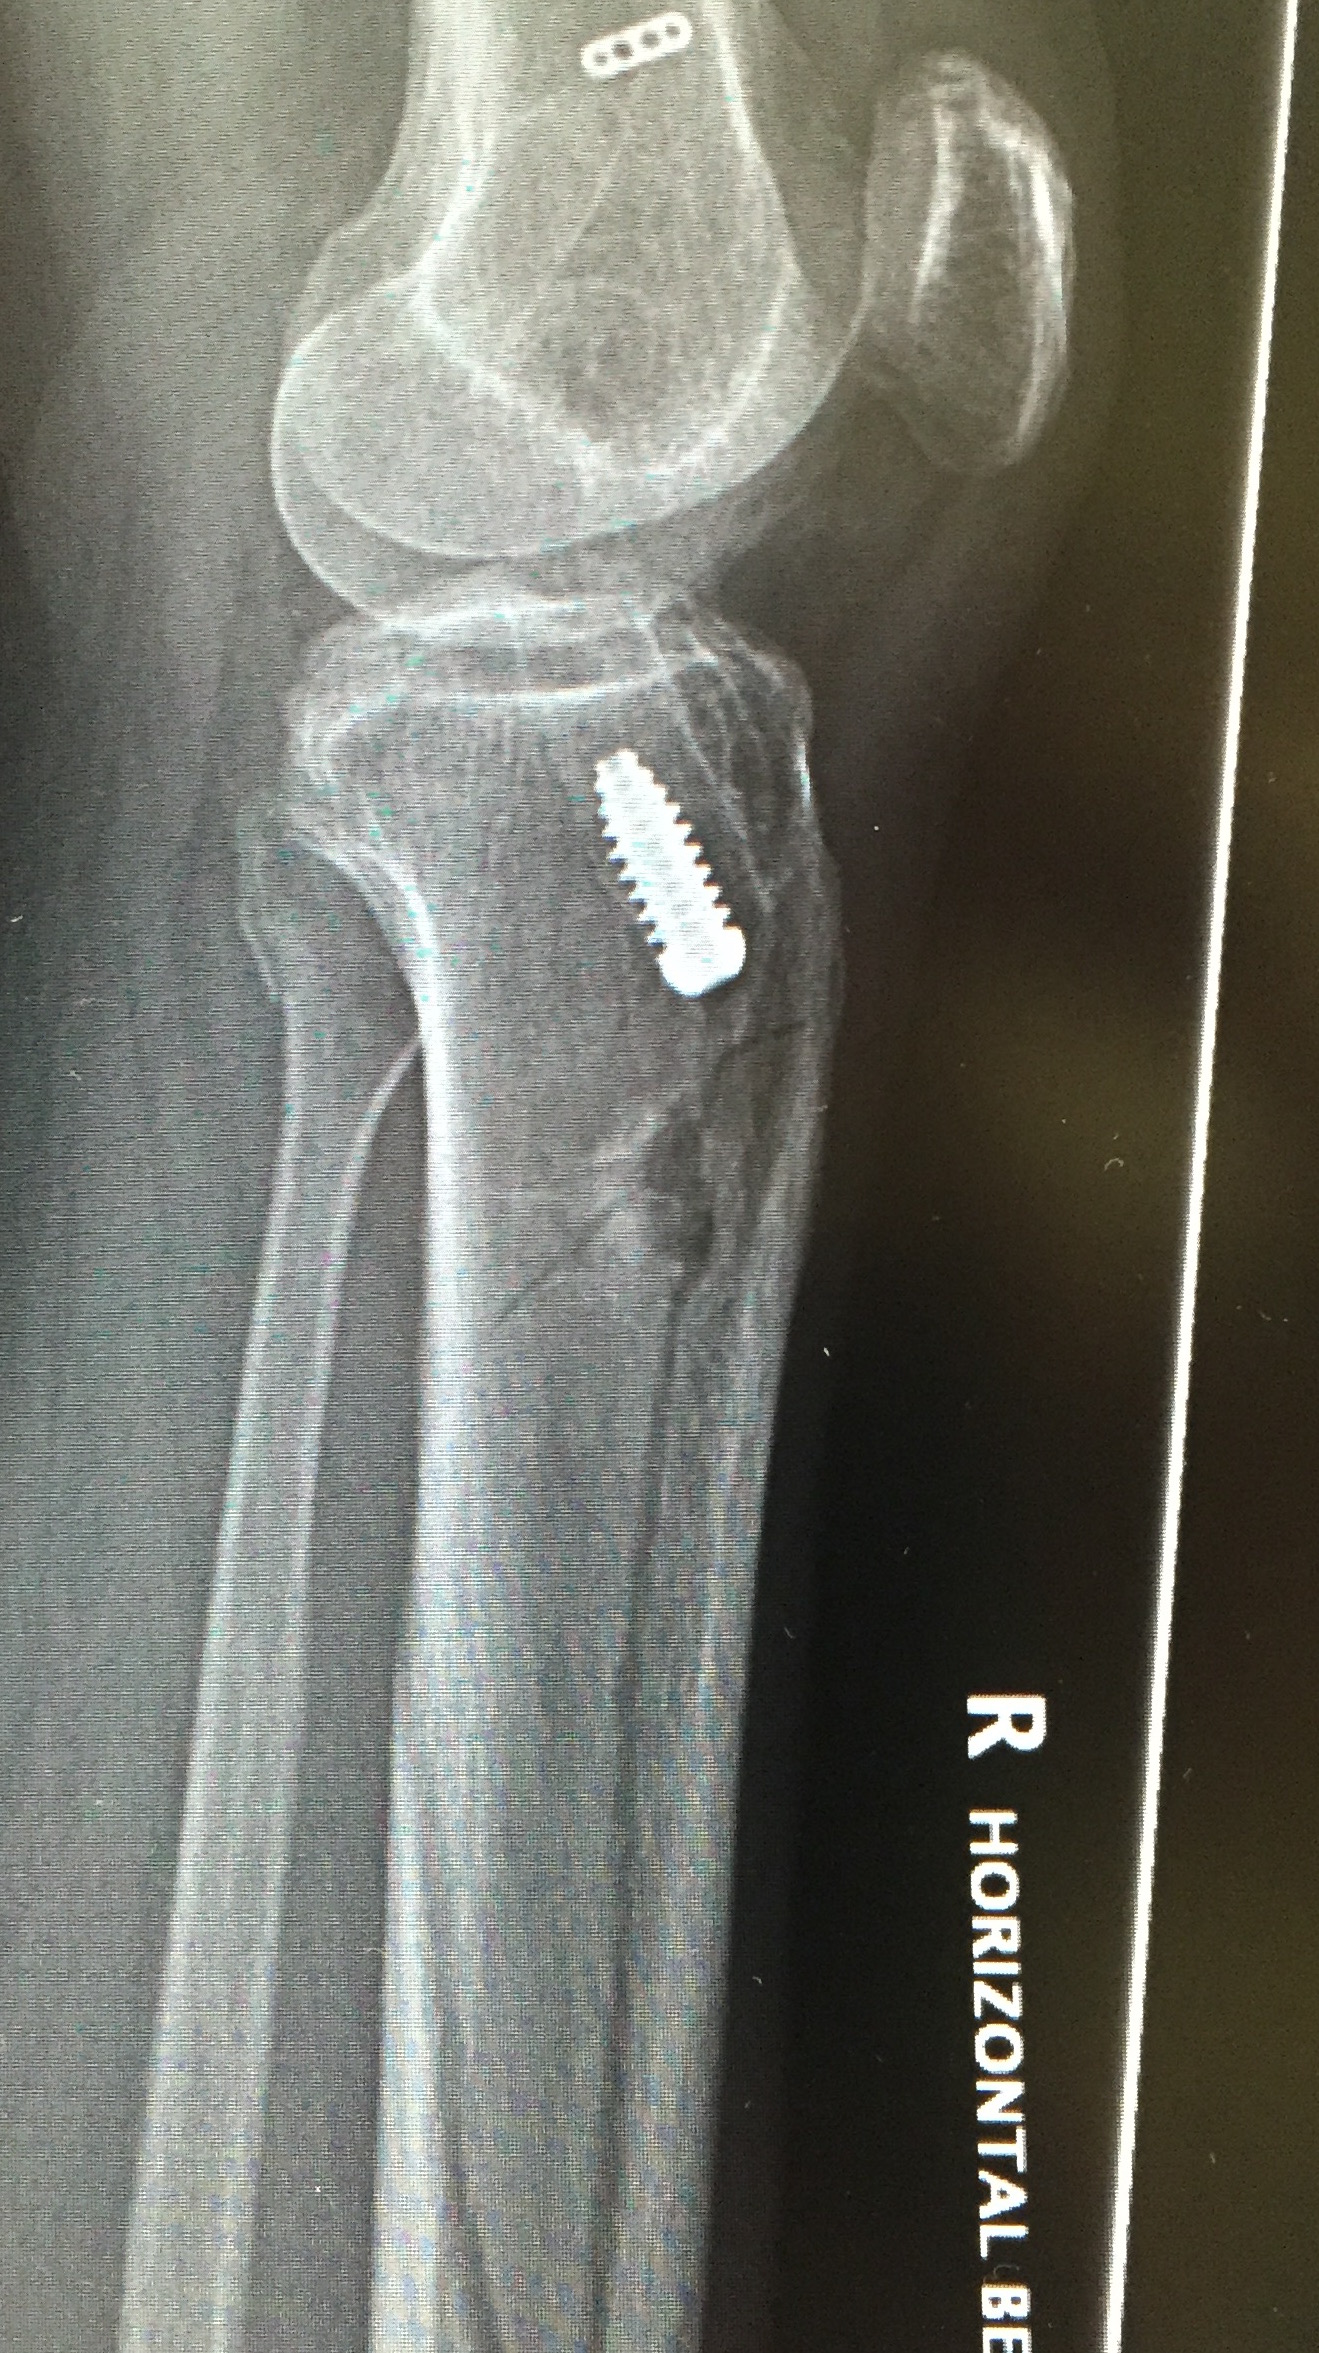

Fracture

Patella fracture

Tibial fracture

If using back up fixation such as a fracture, ensure sufficient distance from tibial tunnel

Alternatively, use a screw-post fixation